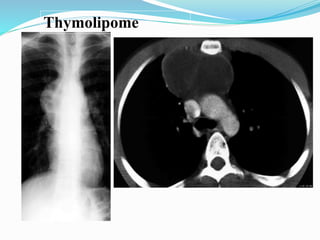

Thymolipome

Tumeur du médiastin